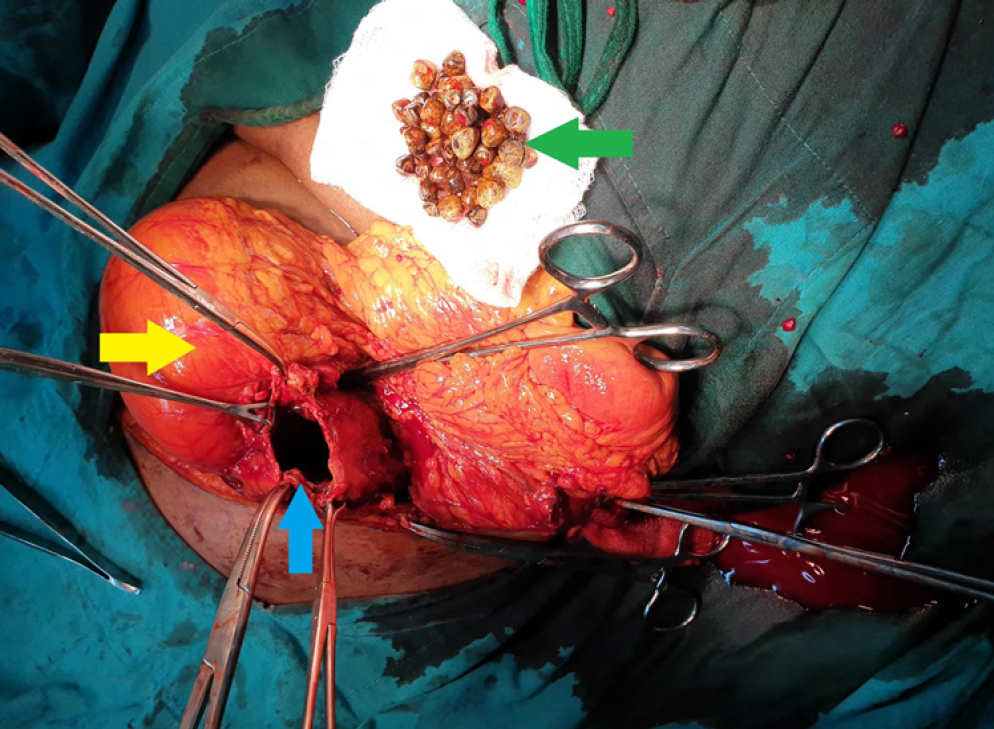

Introduction: Gallbladder carcinoma is a malignant epithelial neoplasm of the gallbladder. The tumor is clinically aggressive, with an overall 5-year survival rate of < 10%. Cholelithiasis is a known and established risk factor. Up to 50% of gallbladder tumors are detected incidentally in routine cholecystectomy specimens due to the absence of gross abnormalities. Gallbladder carcinoma has several unusual presentations, one of which is an incidental pseudocyst with cholelithiasis and perforation. This unusual occurrence makes the index case unique.

Case presentation: We report a case of gallbladder cancer diagnosed by an emergency cholecystectomy, performed for acute cholecystitis caused by a pseudocyst. The patient underwent chemotherapy, and currently, 12 months have passed. The patient is doing well, without signs of recurrence or metastasis.